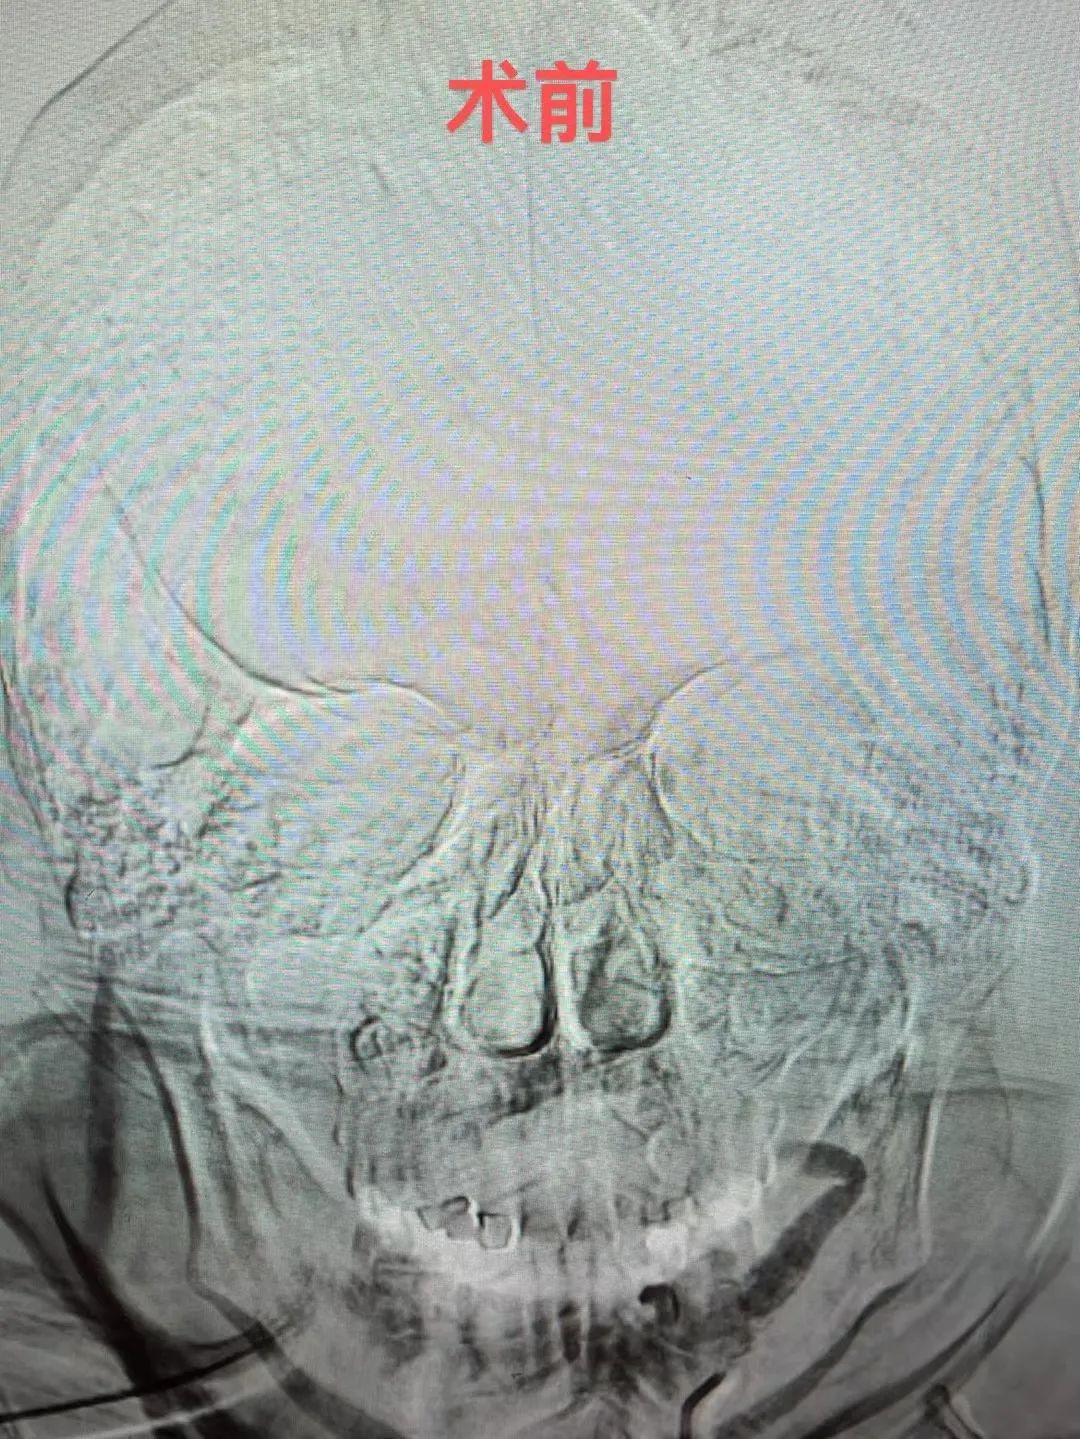

神经介入团队梁达主治医师接到会诊立即到达。他通过查体、综合石奶奶的症状和检查结果,诊断为:大面积脑梗死,左侧颈内动脉、大脑中、前动脉闭塞 、心房颤动、肋骨骨折,病情复杂而危重,考虑存在血栓脱落致急性脑动脉闭塞、静脉溶栓出血等风险,建议急诊直接介入取栓,有生的希望! 缪桂华副主任医师带领团队成员研究制定了手术和麻醉方案。虽然高龄,石奶奶耳聪目明,她的家属都表示非常希望能够尽快手术来挽救生命。

图片

介入导管室一键启动,麻醉科配合采用局麻+药物联合麻醉,缪桂华副主任医师带领团队通过股动脉置管建立手术取栓通道,考虑血栓负荷量大,小心探查,由近及远行ADAPT技术抽吸出血栓主体,颅内残余血栓采用抽吸导管及支架钳夹出来,最终在错综复杂的血管“迷宫”中,找到了一条“生命通道”,手术时间仅用1小时左右,石奶奶被收住入神经内科监护病房继续救治。